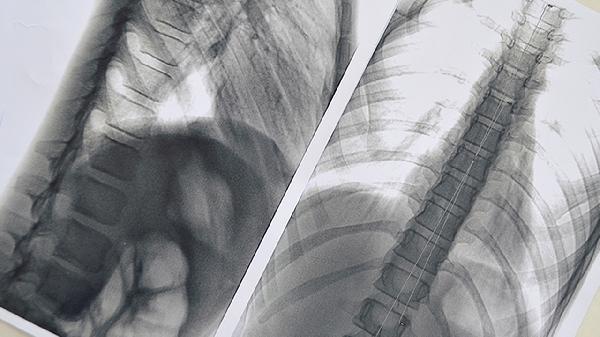

3、下肢无力发麻

癌细胞转移至脊柱压迫神经时,会出现进行性加重的下肢无力感,严重时影响行走。